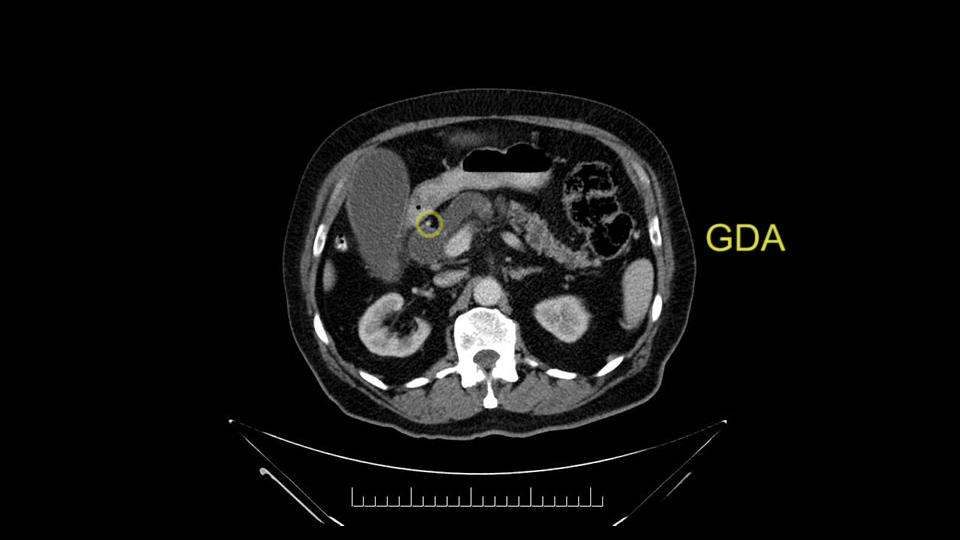

The gastroduodenal artery, a major artery that we have to divide, along with some pancreatoduodenal arteries, may have atherosclerotic changes so they would have to be handled with care, when I attempt what I think would be a pylorus-preserving pancreatoduodenectomy would be the plan. In some cases, I might make an intraoperative change and do a partial antrectomy or a pylorus-resecting Whipple, should the need arise for technical reasons but not because of the size of the tumor.

The other slowing down moment would be the gastroduodenal artery. Confirming that the gastroduodenal artery is not a dominant artery supplying blood to the liver. Liver failure is something which we don’t want due to altered blood supply to the liver or hampered arterial blood supply to the liver. So I would dissect out the hepatic artery, the left and right branches very clearly. Put a bulldog clamp on the gastroduodenal artery, make sure that the perfusion of the liver is excellent on the right and left side, and then divide the gastroduodenal artery. I would avoid using crushing instruments or crushing clamps on the gastroduodenal artery because they have a tendency to shatter in patients who are old with friable vessels so you have to be careful and tackle it with the help of a 5-0 or a 6-0 prolene sutures. In younger patients, I would just apply clips and move on when it comes to dividing the gastroduodenal artery.

First, the stenosis of the celiac trunk, which can be caused by arteriosclerosis, especially in a patient who is 83, or in patients who have arcuate ligament; we do see it, sometimes in much younger patients. In those cases, it may be that the circulation of the hepatic artery comes entirely from the gastroduodenal artery and its anastomoses, through the pancreaticoduodenal arteries, coming from the superior mesenteric artery. This means that before the gastroduodenal artery is ligated, we first clamp and wait 30 seconds to a minute, to feel and check the arterial inflow to the liver. If the pulse is diminished or there is a complete absence of the pulse, the surgery should be modified or probably a pancreatoduodenectomy cannot be done, because of the risk - when ligating the gastroduodenal artery - of causing fulminant hepatic ischemia postoperatively.

I am a believer in pylorus preservation. And in this case I see no reason why that wouldn't be possible. Mobilize the duodenum, divide the gastroepiploic vessels and divide the duodenum. I try to divide it with a linear stapler about four centimeters from the pylorus to have adequate length for my GI anastomosis. This facilitates exposure of the head neck of the pancreas. I find the gastroduodenal artery. This patient has normal arterial anatomy. Always on every preoperative CT scan I look to see if there is a replaced right hepatic. In this case I did not see one. Regardless of how confident I am I always look carefully for variant anatomy. I always do a clamp test on the GDA before ligation. I doubly ligate the GDA with not just a tie but a suture ligature because of the risk of GDA blowout in patients with a leak.